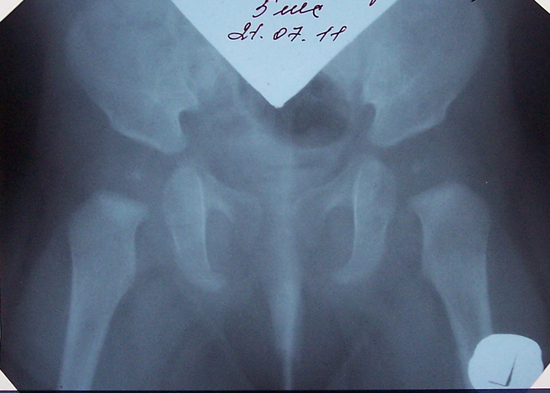

Оссификация тазобедренных суставов: что это и как проявляется?